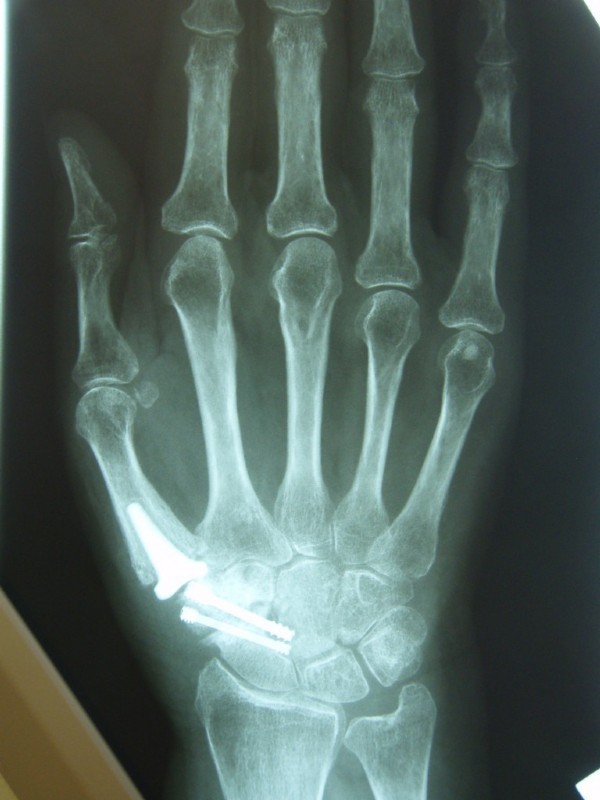

Below: End-joint stiffening in the index finger and middle-joint endoprosthesis in the middle finger

Joint replacement in the wrist area